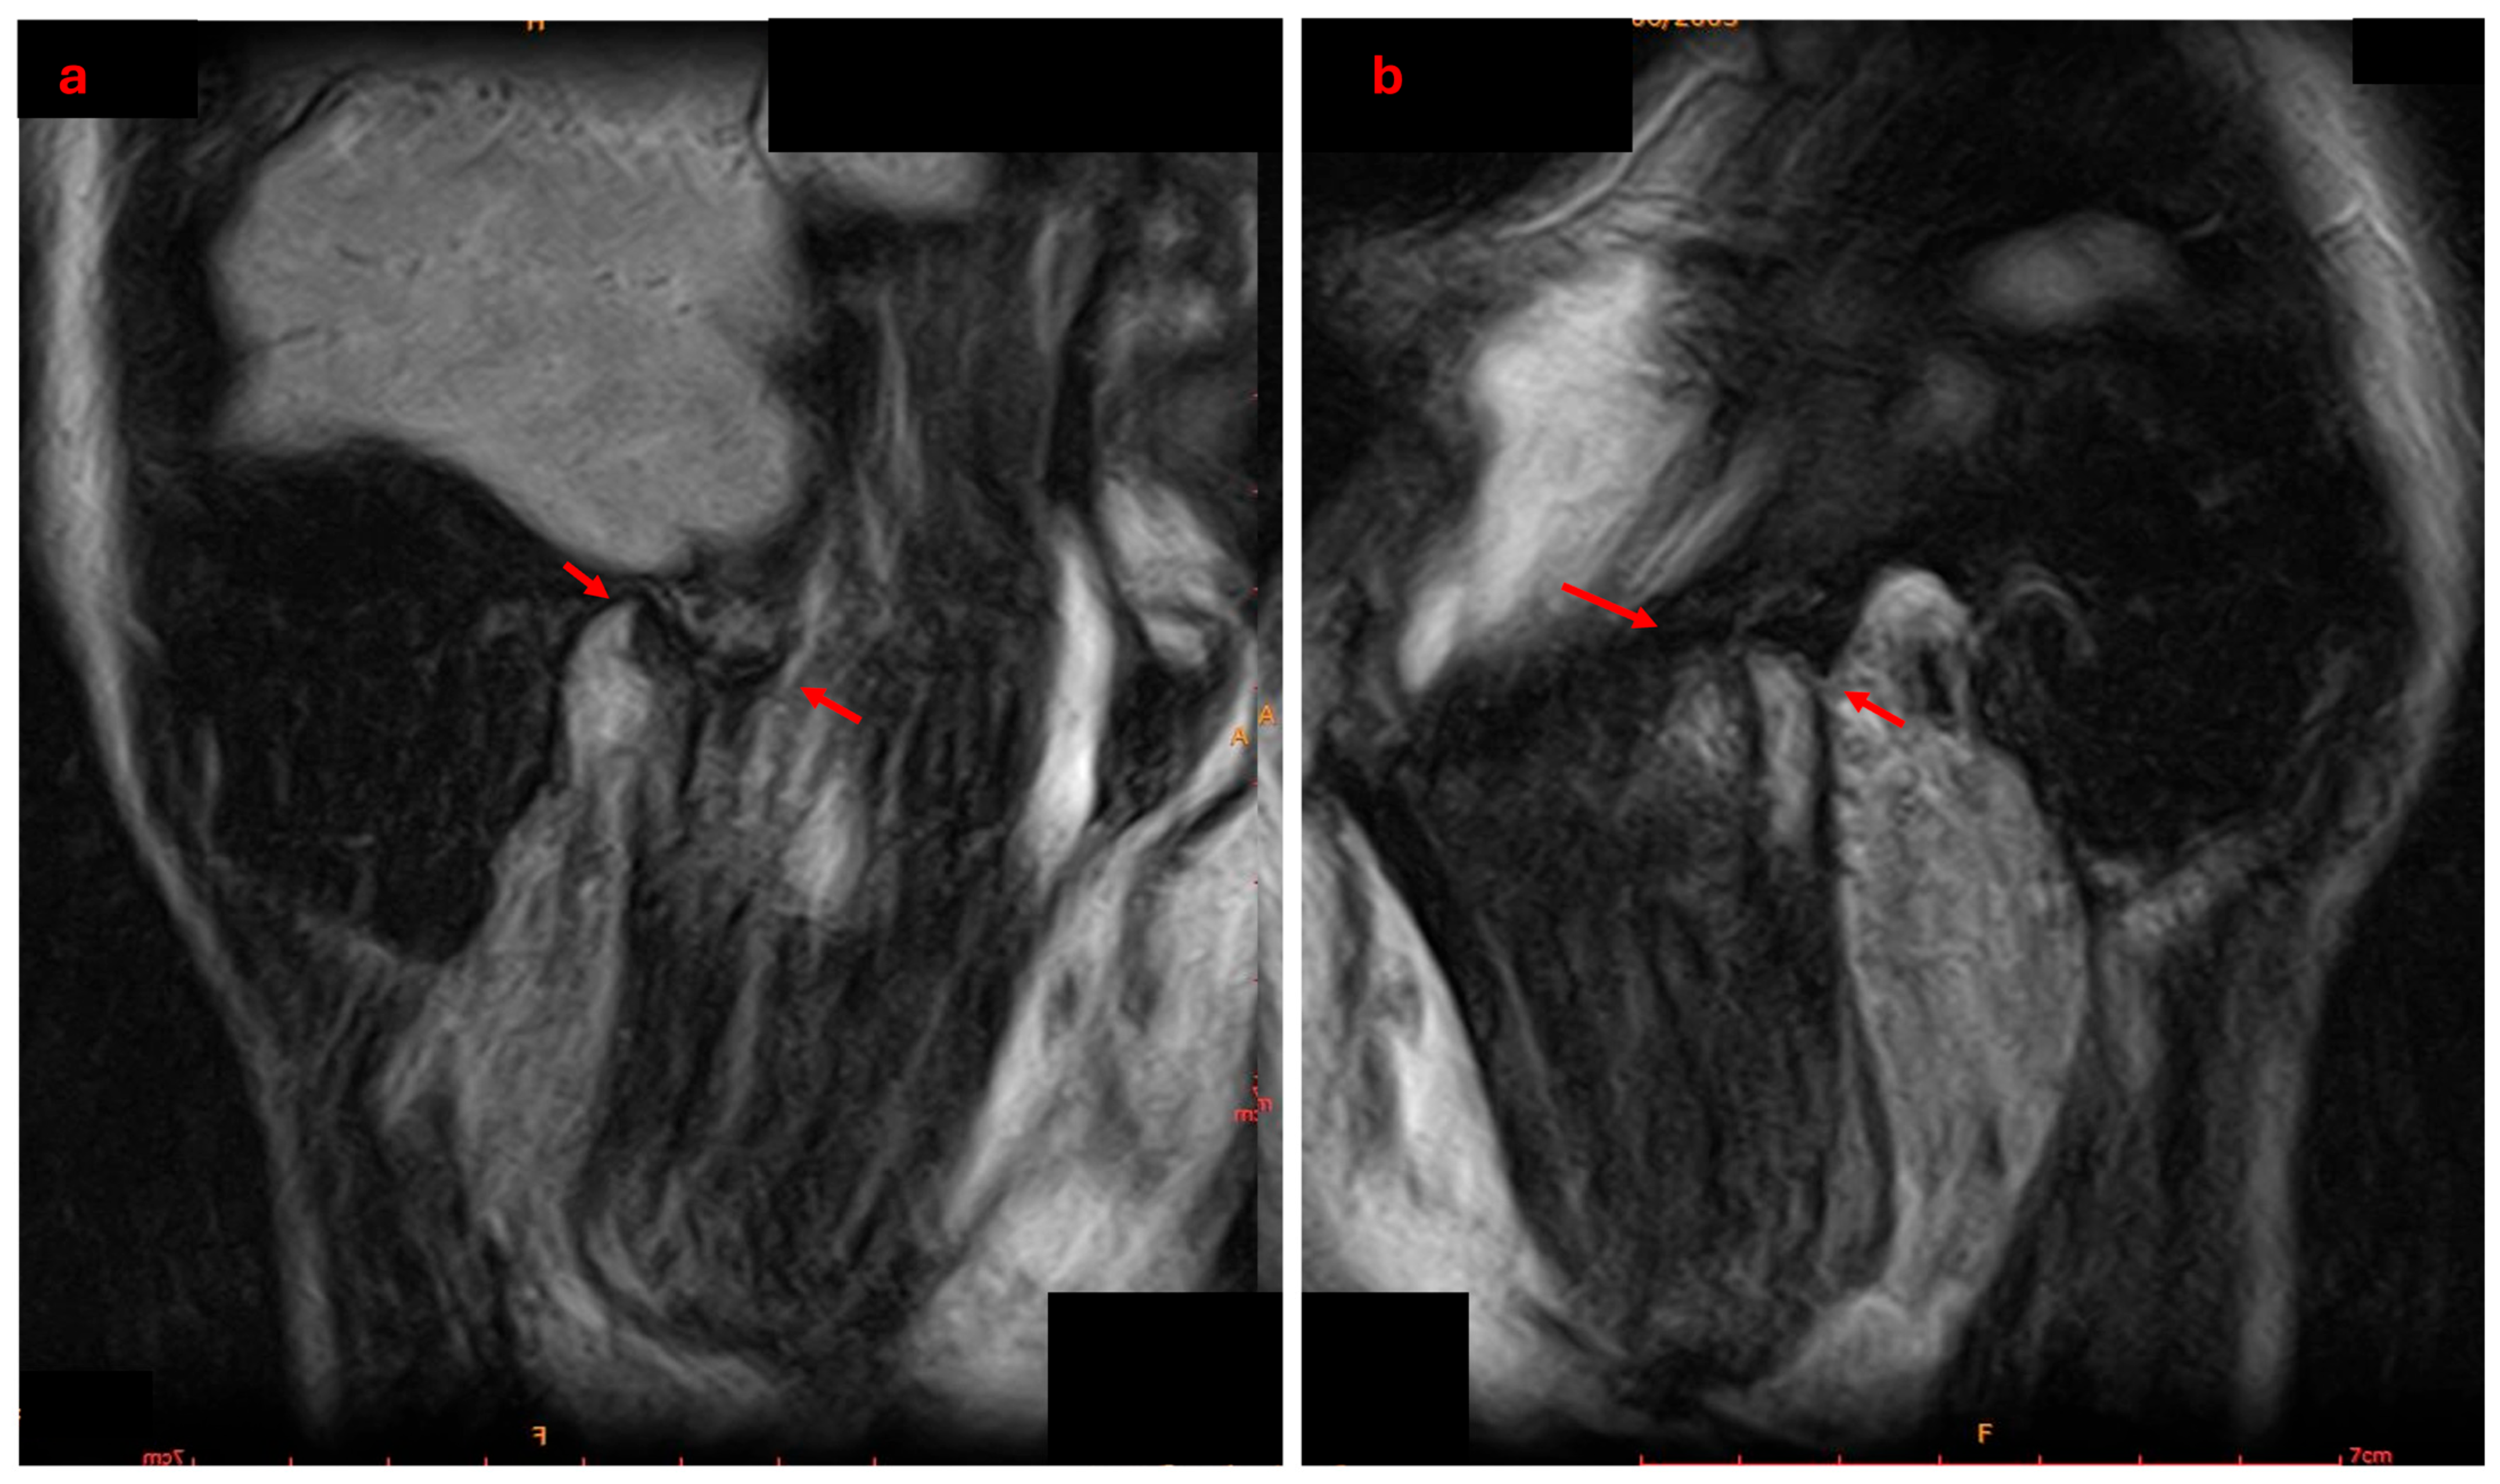

2.4. Diagnosis and Treatment Planning

- Hasan, N.M.A.; Abdelrahman, T.E.F. MRI evaluation of TMJ internal derangement: Degree of anterior disc displacement correlated with other TMJ soft tissue and osseous abnormalities. Egypt. J. Radiol. Nucl. Med. 2014, 45, 735–744. [Google Scholar] [CrossRef]